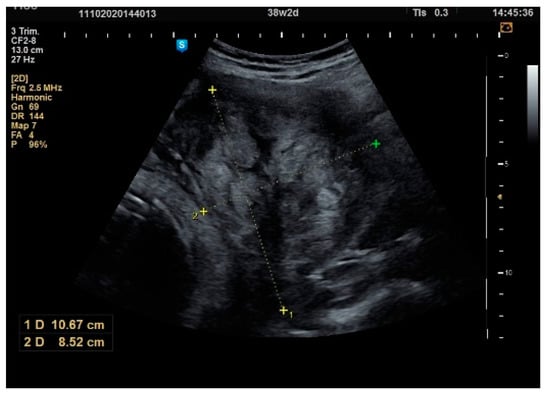

| Size of Fibroid, mm | ||||

| Antepartum | 1st Trimester | 2nd Trimester | 3rd Trimester | |

| N | 55 | 49 | 50 | 53 |

| Mean | 40.02 | 44.51 p = 0.005 * | 54.76 p = 0.001 * | 61.58 p = 0.001 * |

| Difference from the previous average | - | +4.49 mm (+11.2%) | +10.25 mm (+23.0%) | +6.92 mm (+12.6%) |

| Median | 38 | 40 | 50 | 60 |

| Std. Deviation | 18.29 | 17.21 | 21.37 | 24.54 |

| Minimum | 20 | 20 | 20 | 25 |

| Maximum | 90 | 90 | 100 | 160 |